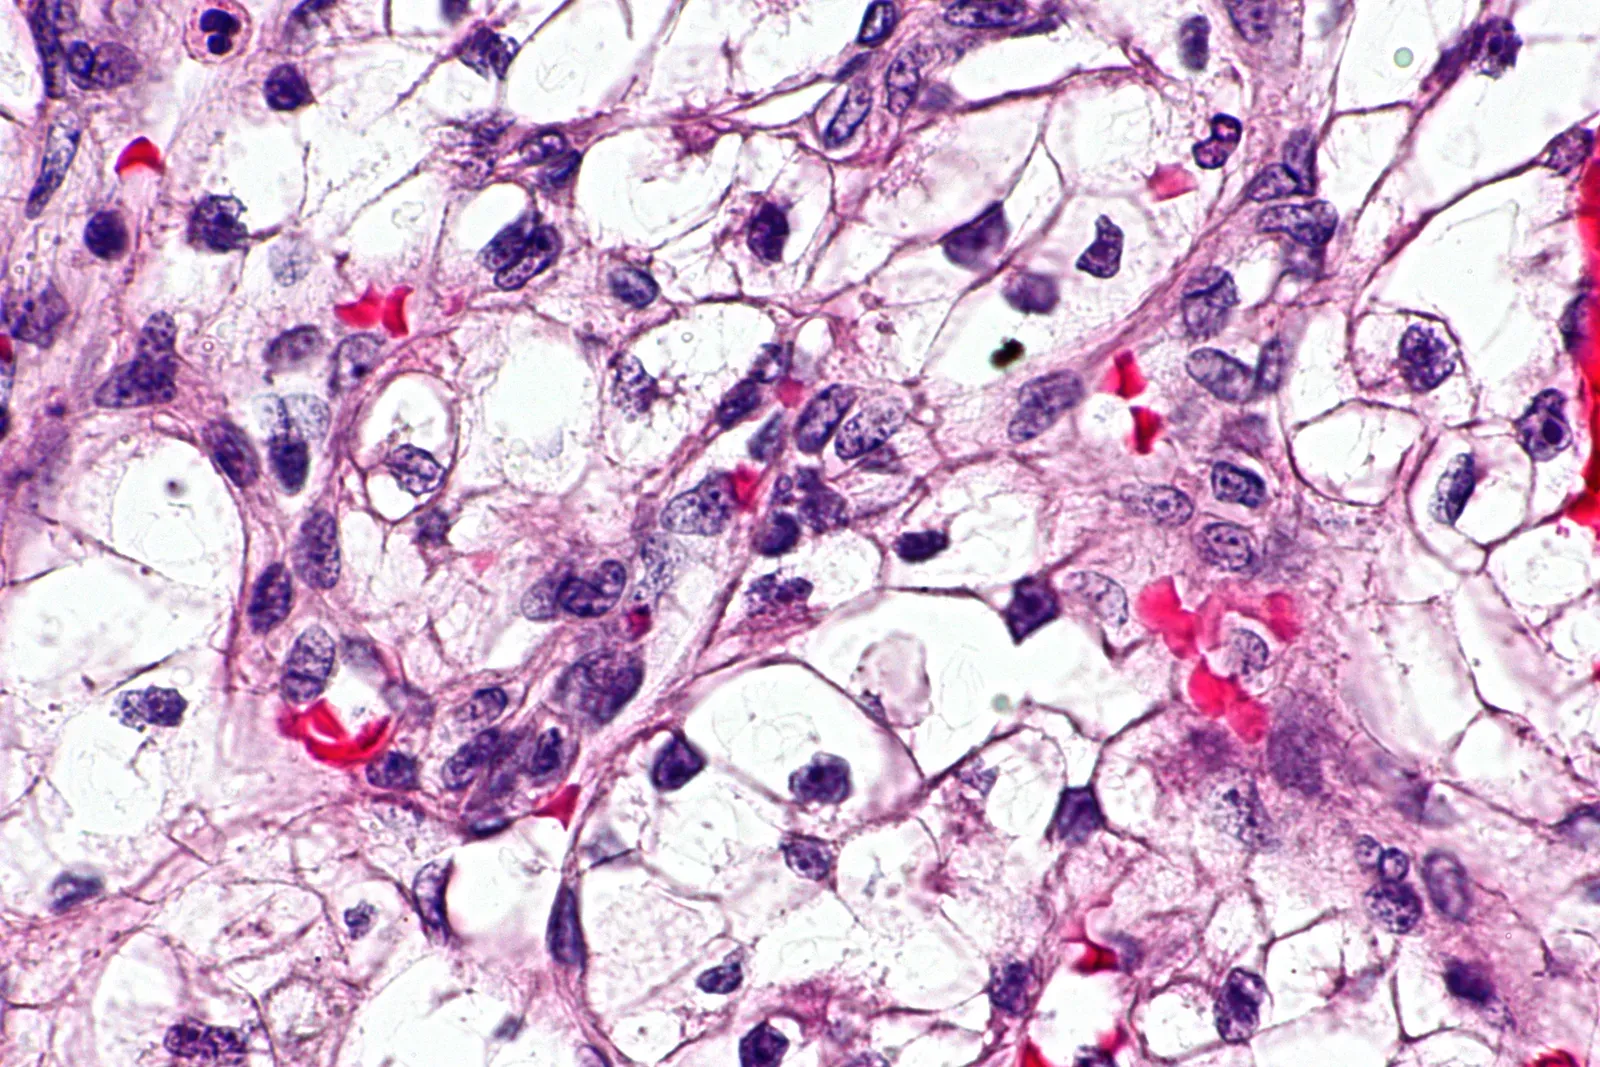

Memory Is Not Just Stored in Your Brain

Here’s the thing – this might be the most mind-blowing discovery to come out of memory research in recent years, and it’s still not widely known. It turns out your brain might not be the only part of your body that remembers. Scientists at NYU have found that cells outside the brain, like those from your kidneys, can actually “learn” and form memories. By mimicking how the brain processes information using spaced repetition, researchers showed that even non-brain cells can activate a key memory gene in response to patterns.

This suggests memory isn’t just a brain thing – it might be a basic feature of many cells in the body. Researchers discovered that even kidney and nerve tissue cells can detect learning patterns and activate a memory gene, just like neurons do. This opens new possibilities for enhancing learning and treating memory conditions. Think of it as your whole body quietly taking notes, even when your brain isn’t paying attention. The implications for medicine and our understanding of intelligence are still being untangled.